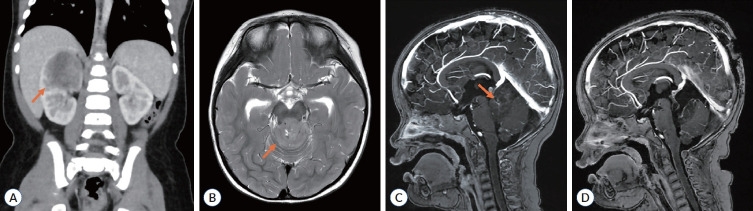

Rhabdoid tumor predisposition syndrome (RTPS) is a rare autosomal dominant disorder characterized by an increased risk of developing malignant rhabdoid tumors in early childhood. This syndrome is primarily caused by germline heterozygous loss-of-function pathogenic variants in the SMARCB1 gene (RTPS1) and rarely in the SMARCA4 gene (RTPS2). RTPS is characterized by the development of atypical teratoid rhabdoid tumors of the central nervous system, malignant rhabdoid tumors of the kidney, and/or extrarenal extracranial rhabdoid tumors. The syndrome demonstrates high penetrance, with most tumors developing before age 3 years, and carries a poor prognosis despite intensive multimodal therapy. Early diagnosis through genetic testing, implementation of surveillance protocols, and aggressive treatment approaches are crucial for improving outcomes. This review comprehensively examines the genetic basis, clinical manifestations, surveillance strategies, and current management approaches for RTPS, with particular emphasis on emerging therapeutic options and the importance of multidisciplinary care.